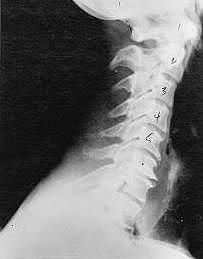

Phase One - Subluxation Degeneration

Subluxation Degeneration - Phase One Phase One Subluxation Degeneration is seen in subluxations that have been present for up to twenty years. This phase is characterized with a loss or change in the normal curve in the spine. On this example you can see that the normal forward (lordotic) curve is lost. This spine even has developed a reverse curve in the neck. The disc spaces have also begun to exhibit a slight change in shape. One good point is that the bodies of each of the vertebrae (the square part in front) still exhibits clean clear borders. Segmental motion may be abnormal but overall motion is probably not affected. Chiropractic reconstructive care for a phase one can take from 6 to 18 months. More than 80% of people with Phase One Subluxation Degeneration have no pain. Therefore, if left uncorrected, phase one continues to progress with time until it eventually reaches the next phase.